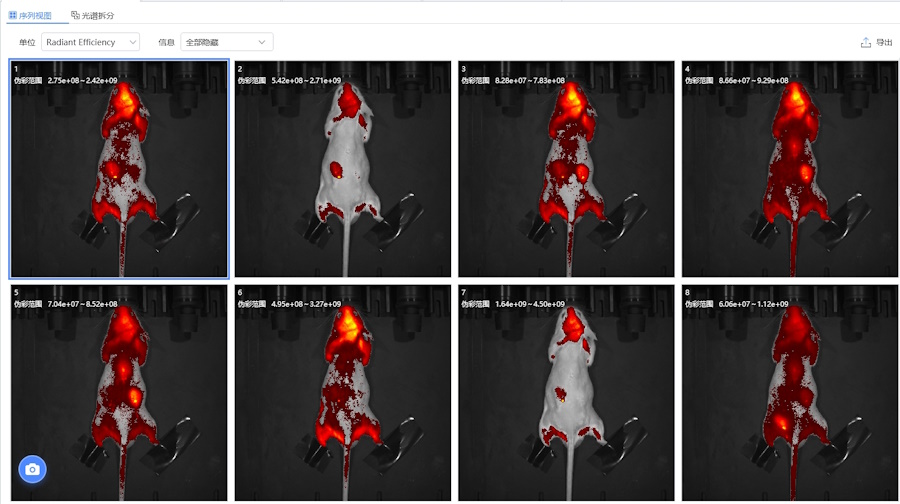

Система MOIS в исследованиях биолюминесценции

- Мониторинг хода заболевания в живом организме, изучение с помощью изображений распространение и роста опухолевых клекток;

- определение эффективности и биологического распределения лекарственных препаратов, частиц наноформата и других молекул;

MOIS HT визуализирует флуоресценцию в видимом (VIS) и инфракрасном (NIR) спектре, биолюминисценцию in vivo и in vitro